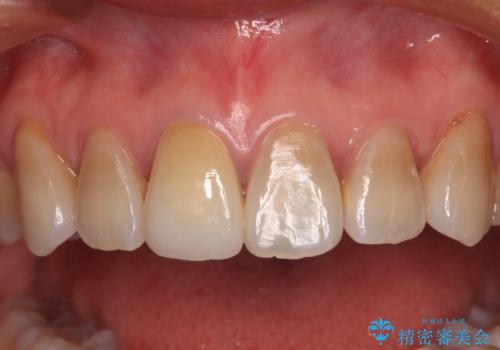

- 結婚式を前に、保険診療での前歯のクラウンが気になるとのことで来院された患者様です。

色合いだけでなく、歯肉の縁が黒くなっていることが分かります。

速やかに仮歯に交換し、オールセラミッククラウンにて補綴することとしました。

神経組織が健全な状態で残っている歯であったため、1ヶ月かからずに治療を終えることができました。